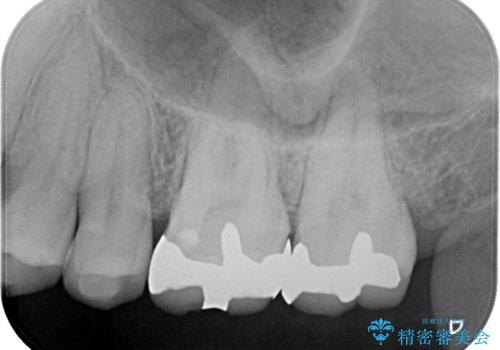

【メタルフリー】セラミックインレーの修復

- メタルフリーを希望された患者さんです。

金属を除去し虫歯の処置をしたあとセラミックインレーにて修復しました。